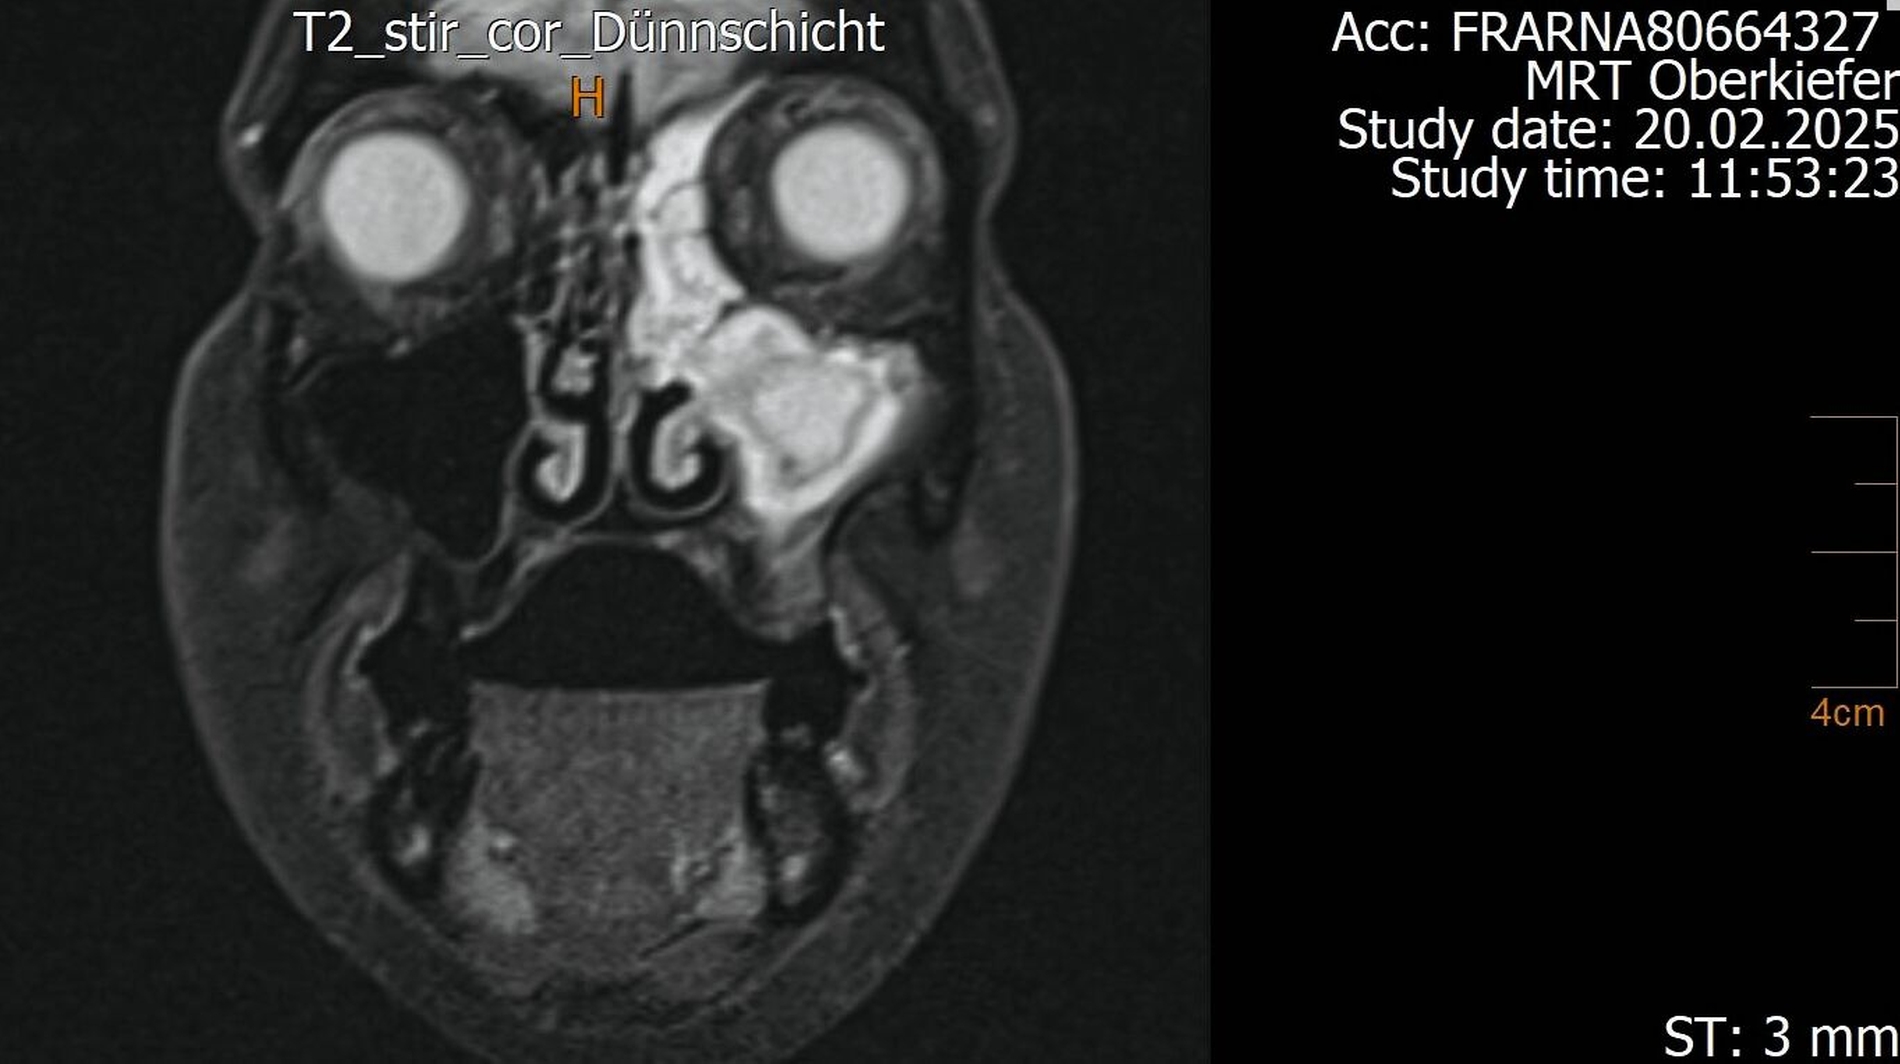

Der Wendepunkt erfolgte schließlich im Februar 2025 im Rahmen einer Kontrolluntersuchung bei der Hauszahnärztin. Diese nahm die langjährige Beschwerdesymptomatik ernst und veranlasste eine MRT-Untersuchung am Deutschen Zentrum für Dentaldiagnostik (DZD). Die MRT-Bildgebung ergab eine chronische Osteomyelitis im Bereich der Extraktionsregion von Zahn 27 sowie eine ausgeprägte apikale Ostitis an Zahn 26 mit vollständiger Verschattung der linken Kieferhöhle und Ausdehnung der Entzündung ins Siebbein und in die Stirnhöhle. Auch konnte durch den befundenden Radiologen eine interradikuläre Fistelung an Zahn 26 erkannt werden, weshalb die Sinusitis als odontogen eingestuft wurde (Abbildungen 4 bis 7).

In speziellen Fällen kann ergänzend eine MRT sinnvoll sein – etwa bei unklarer Symptomatik, bei Verdacht auf Weichteilbeteiligung, bei einem chronisch-rezidivierenden Verlauf oder bei unzureichender Abgrenzbarkeit im DVT. Im vorgestellten Fall ermöglichte die MRT den Nachweis des interradikulären Fistelgangs zur Kieferhöhle und damit die korrekte Zuordnung des Entzündungsfokus.